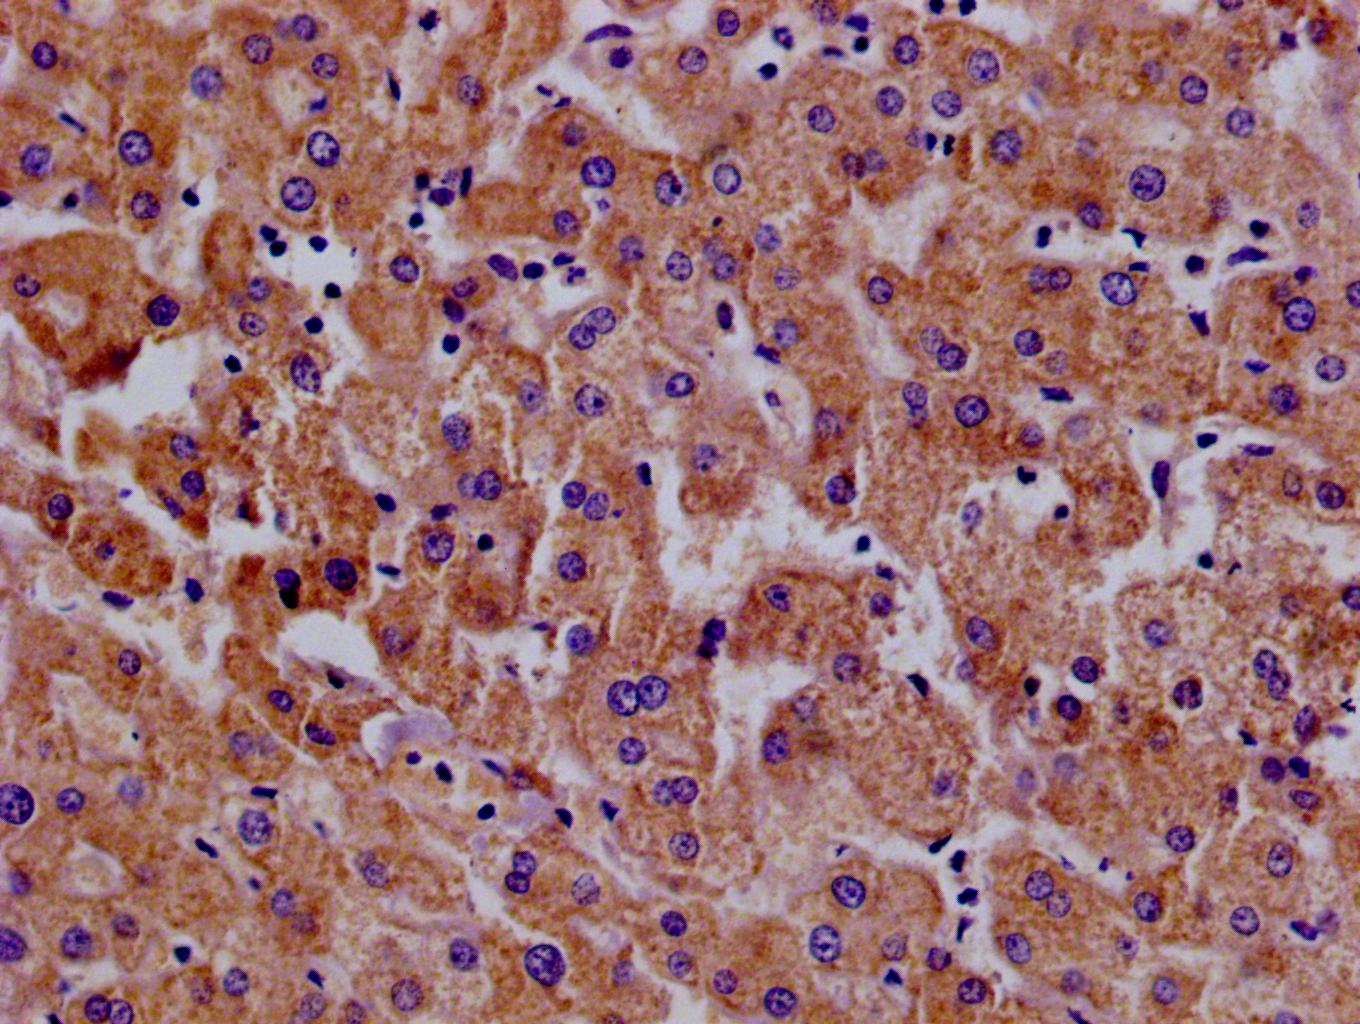

Immunohistochemistry of paraffin-embedded human liver tissue using CSB-PA015249LA01HU at dilution of 1:100